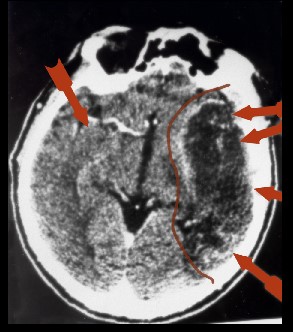

Der erste entdeckte „Hamersche Herd“

Bereits 1982 gelang es mir – also ein Jahr nach der Entdeckung der Germanischen Heilkunde (damals noch „Eiserne Regel des Krebs“) – schon prospektiv einen Hamerschen Herd (HH) riesigen Ausmaßes bei einem Patienten mit Revierkonflikt in der Heilungsphase und Herzinfarktgeschehen in der epileptoiden Krise zu finden.

Von da ab wusste ich, dass es keine Hirntumoren gab, sondern dass diese Phänomene alle im Zusammenhang mit der Lösungsphase eines biologischen Konfliktgeschehens stehen mussten.

Der Patient, zu dem diese Bilder gehören, war der allererste, bei dem ich prospektiv einen später sog. „Hamerschen Herd“ suchte und auch fand.

Der Patient hatte in diesem Moment drei DHS erlitten:

einen Revier-Konflikt,

einen Revier-Ärger–

einen Revier-Angst-Konflikt.